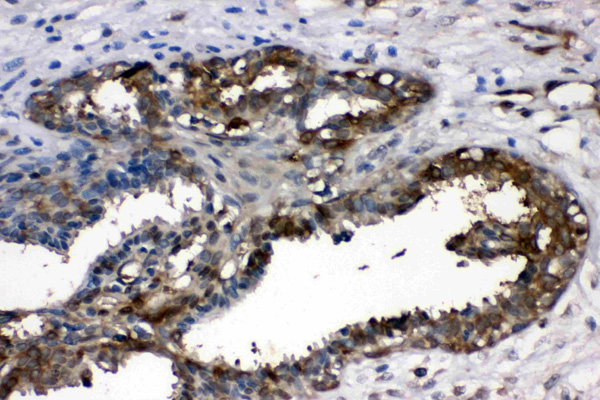

(LDHA was detected in paraffin-embedded sections of rat intestine tissues using rabbit anti- LDHA Antigen Affinity purified polyclonal antibody at 1 ug/mL. The immunohistochemical section was developed using SABC method.)